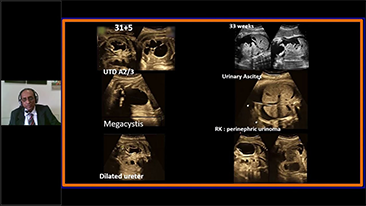

Los flujos de trabajo de OBG optimizados son necesarios para admitir grandes cantidades de pacientes para las visitas de evaluaciĂłn de la salud de las mujeres. Por ejemplo, las malformaciones del sistema nervioso central (SNC) son una de las anomalĂas congĂ©nitas mĂĄs comunes. Debido a las diversas condiciones del diagnĂłstico por imĂĄgenes, como una posiciĂłn fetal deficiente, el plano sagital medio (MSP) es particularmente difĂcil de obtener a partir de una ecografĂa 2D. Por lo tanto, la detecciĂłn y las mediciones automatizadas pueden mejorar en gran medida la eficiencia de la exploraciĂłn.